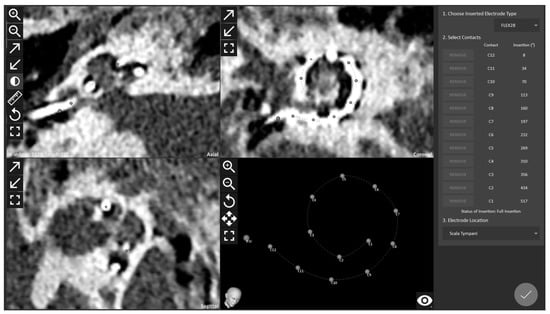

- Topsakal, V.; Heuninck, E.; Matulic, M.; Tekin, A.M.; Mertens, G.; Van Rompaey, V.; Galeazzi, P.; Zoka-Assadi, M.; van de Heyning, P. First Study in Men Evaluation of a Surgical Robotic Tool Providing Autonomous Inner Ear Access for Cochlear Implantation. Front. Neurol. 2022, 13, 804507. [Google Scholar] [CrossRef]

- Topsakal, V.; Matulic, M.; Assadi, M.Z.; Mertens, G.; Van Rompaey, V.; Van de Heyning, P. Comparison of the Surgical Techniques and Robotic Techniques for Cochlear Implantation in Terms of the Trajectories Toward the Inner Ear. J. Int. Adv. Otol. 2020, 16, 3–7. [Google Scholar] [CrossRef]

- Tekin, A.M.; Matulic, M.; Wuyts, W.; Assadi, M.Z.; Mertens, G.; van Rompaey, V.; Li, Y.; van de Heyning, P.; Topsakal, V. A New Pathogenic Variant in POU3F4 Causing Deafness Due to an Incomplete Partition of the Cochlea Paved the Way for Innovative Surgery. Genes 2021, 12, 613. [Google Scholar] [CrossRef]